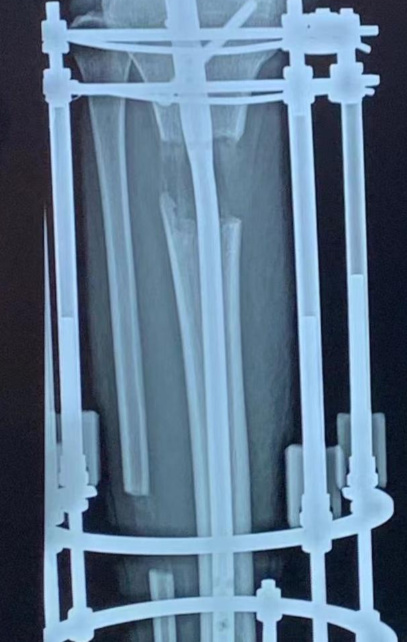

本文聚焦全球增高领域核心技术与材料发展脉络,深度对比医疗级断骨增高技术(肢体延长术)与辅助型增高材料的适配场景,重点解析 Paley 研究院 PRECICE®/STRYDE® 电磁内置髓内钉技术与 Ilizarov 外固定架、德国 FITBONE、韩国 LON + 骨髓移植等主流方案的差异。